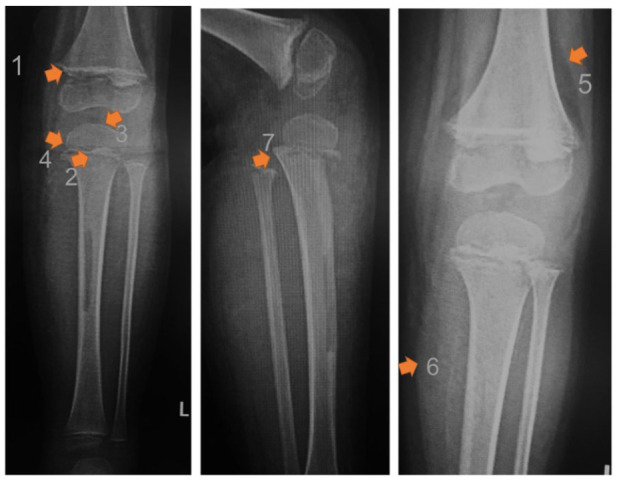

Results: Eighteen cases (17 males, 1 female) of scurvy were referred to our institution. Thirteen of 18 patients were misdiagnosed before referral. The median age at presentation was 4.5 (range, 2-11) years. The average body mass index was 13.93 ± 0.63 kg/m2. Half of patients had healthy weight. All patients presented with lower limb pain and 17 of 18 with refusal to walk. The median onset of diagnosis was 11 (range 4-48) weeks. White line of Frankel was described in all patients. Seven had anemia and 6 of 18 had increase in erythrocyte sedimentation rate and/or C-reactive protein levels. Only one patient had ascorbic acid levels evaluation before treatment since it was not readily available in our country. Treatment length varied from 2 weeks to 6 months.

Abstract Image